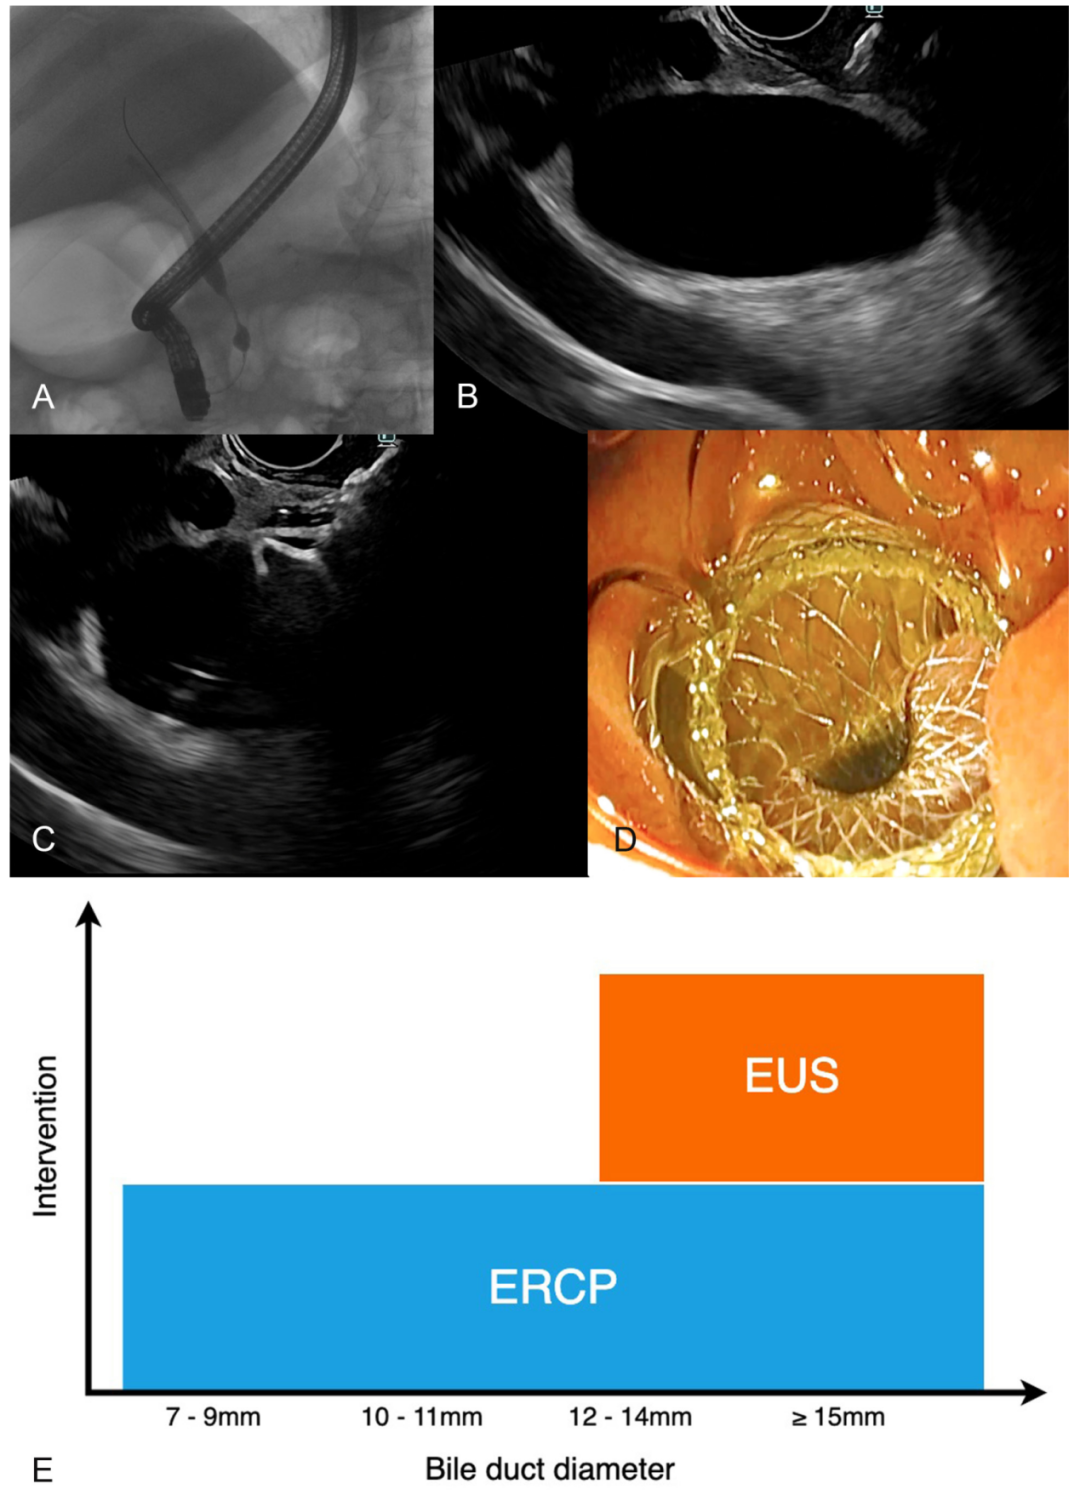

胆管直径是EUS-BD成为一线治疗方案的核心限制因素

近年来,EUS-BD技术快速发展,关于其能否成一线治疗取代ERCP的争议持续存在。一项对439例接受ERCP的远端恶性胆道梗阻患者进行的回顾性研究显示,44.9%患者胆总管(CBD)直径<12 mm,受限于现有技术无法安全行EUS-CDS;ERCP一线成功率达92.5%,失败病例中转EUS-BD成功率87.9%,且EUS-BD组中位CBD直径(16 mm)显著大于ERCP组(11 mm)。研究表明,基于当前技术局限,EUS-BD仅适用于约60%胆管充分扩张的患者,不宜取代ERCP成为所有远端恶性胆道梗阻的首选引流方式,但其作为ERCP失败后的高效补救手段具有重要临床价值。